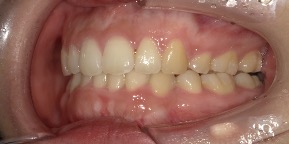

29歳女性のビフォーアフター

| 診断 | 叢生(デコボコがある状態)、過蓋咬合 |

| 治療方針 | インビザラインシステムにて主にIPR(歯と歯の間をわずかに削合してスペースを獲得する方法)を組み込んだ動的矯正治療を行い、叢生を改善後、保定を行う。臼歯部の咬合関係はプランの関係上維持して叢生と前歯部の咬合改善を目指した。 |

| 治療費 ※ | 60万4千円(診断、型取り、PMTC、保定装置を含む料金) |

| 治療期間 | 1年5か月 |

| リスク | 1日20時間以上マウスピースを使用できない場合、歯が動かない可能性がある。装着時や食事時に痛みを伴う。歯肉退縮や虫歯になるおそれがある。また、指導通りに装着できていない場合や適切なブラッシングが出来ていないとそのリスクが高くなる。歯根が短くなることがある。ごくまれに歯の神経が損傷してしまうことがある。過去にぶつけたり深い虫歯治療をしたことがあるとそのリスクはやや高くなる。矯正後には保定装置が必要。適切な使用ができない場合、後戻りの原因となる。将来的に歯並びが動いて再矯正が必要な場合がある。親知らずが正常に生えていない場合、その可能性がやや高くなる。 |

※ 治療費は、治療当時の費用で、現在の費用と異なる可能性があります。現在の費用は治療費のページでご確認くださいませ。